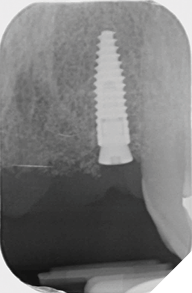

Eight weeks after extraction of the UR1 and UL2 we radiographically assessed the hard tissue healing. The soft tissues had matured well, with good volume of keratinized mucosa and we felt it appropriate to proceed with the implant placements (Figs. 8-9).

Fig. 8

Fig. 9